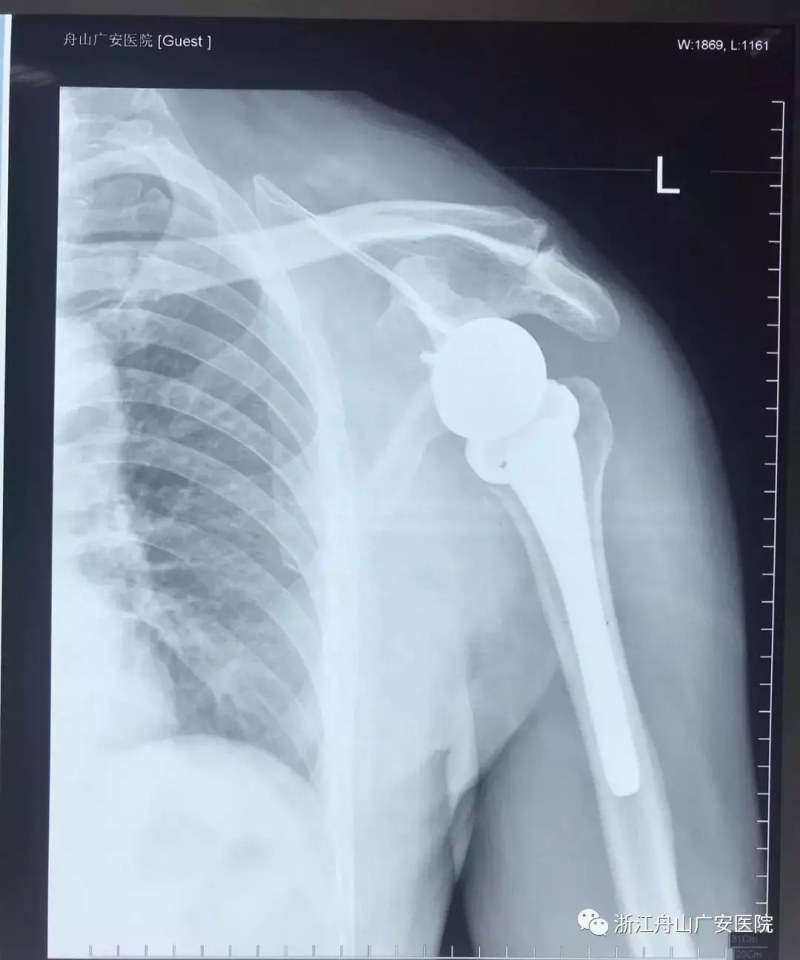

反式肩關節(jié)置換術后照片

經過術前精心的手術準備,羅軍主任帶領手術專家團隊為張大伯做了反式人工肩關節(jié)置換術。手術過程十分順利,僅用時一個半小時,且手術刀口很小,約10cm,術后恢復快,第二天查房時候張大伯便能佩戴特制的肩肘墊起床活動,術前肩關節(jié)劇痛也大大緩解減輕,術后兩周患者功能恢復良好。